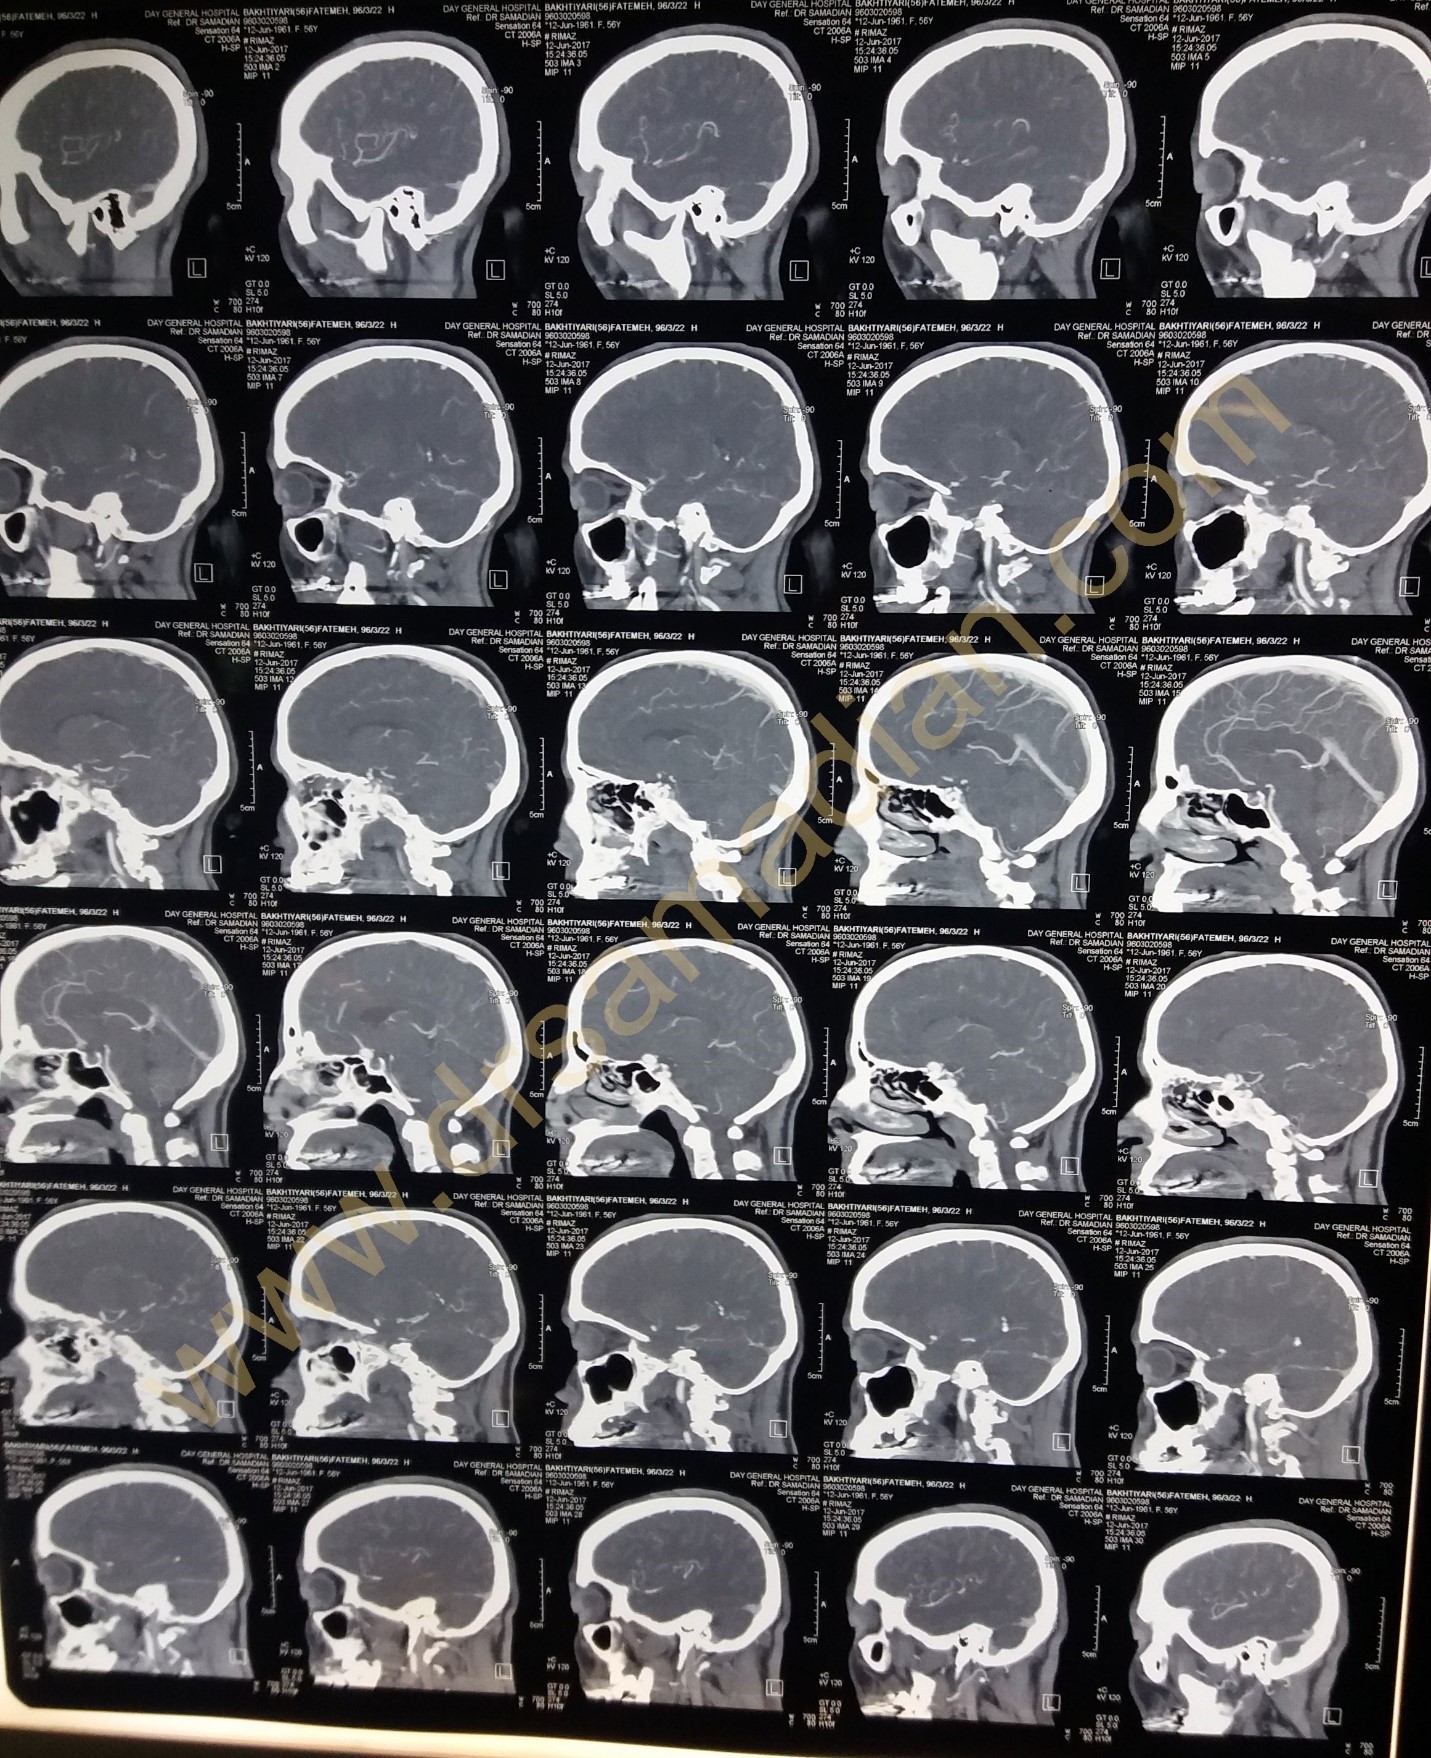

تصاویر یک بیمار آنوریسم مغزی را در زیر مشاهده میکنید :

کلیپ عمل جراحی آنوریسم به صورت میکروسکوپی

بیمار خانم ۵۶ ساله که از بیماران قدیمی بوده که به علت دیسک کمر چند سال قبل عمل شده بودند به علت کاهش بینایی چشم راست مراجعه کرده در بررسیها تشخیص آنوریسم بزرگ شریان کاروتید راست داشتند و نیز پس از بررسیهای کامل تحت عمل جراحی کلیپ آنوریسم به صورت میکروسکوپی قرار گرفتند بینایی بیمار بهتر شد و عارضه خاصی نداشت.